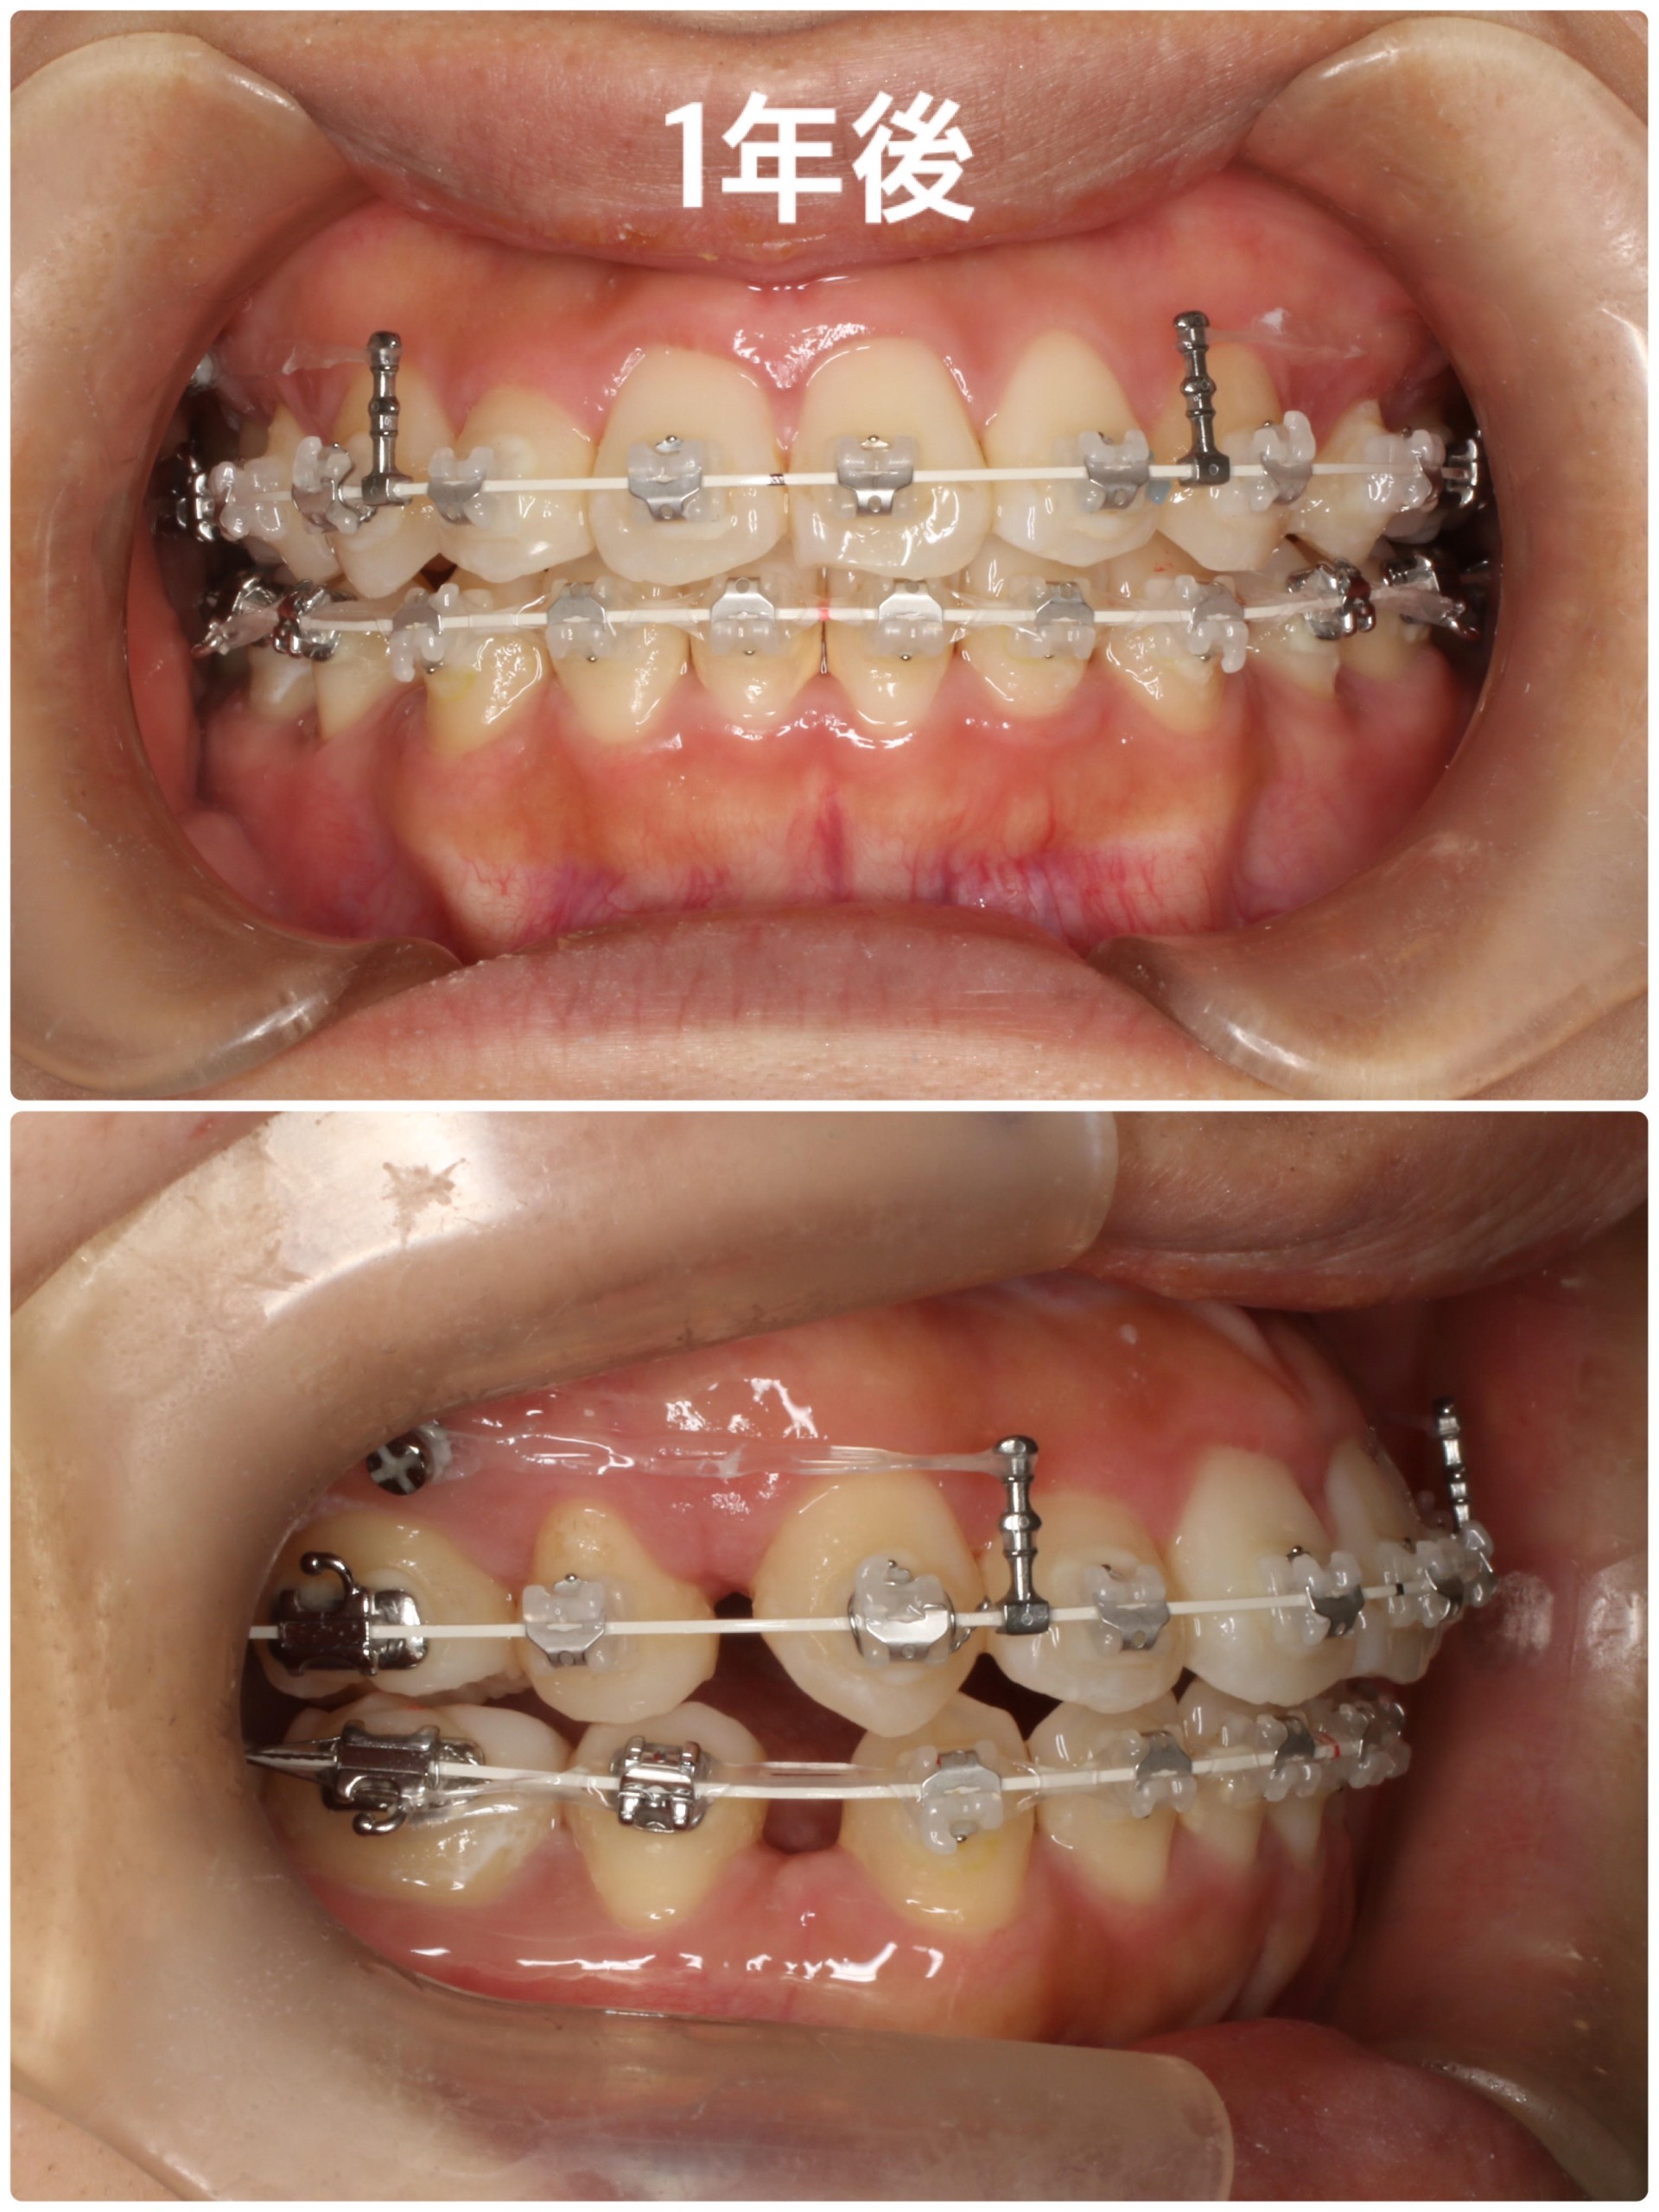

【1年後】

治療を開始してから約1年が経過しました。半年の時点では並びきっていなかった上顎右側の2番もしっかりと他の歯と並び、太いワイヤーを通してあります。

上のワイヤーの左右に2本の棒のようなものがセットされていますが、この棒から固定源であるTADsまでを半透明の『パワーチェーン』と呼ばれる輪っかが連続したようなゴムで繋ぐことで抜歯した部分の隙間を閉じていきます。写真では見えにくいですが、下の方にも隙間を閉じていくためのパワーチェーンが装置にかけられています。

隙間が閉じるスピードにはかなり個人差がありますが、大体1ヵ月に1ミリ程度とされています。隙間を閉じるフェーズでは毎月の調整の際に隙間の測定とパワーチェーンの交換を行っており、隙間の閉じ具合によってパワーチェーンの強さを変えることもあります。

また、この時点では上下の正中もずれてしまっているので、正中を合わせるために『エラスティックス』という矯正用の小さな輪ゴムのようなものを用いてゴムかけをしていただきます。